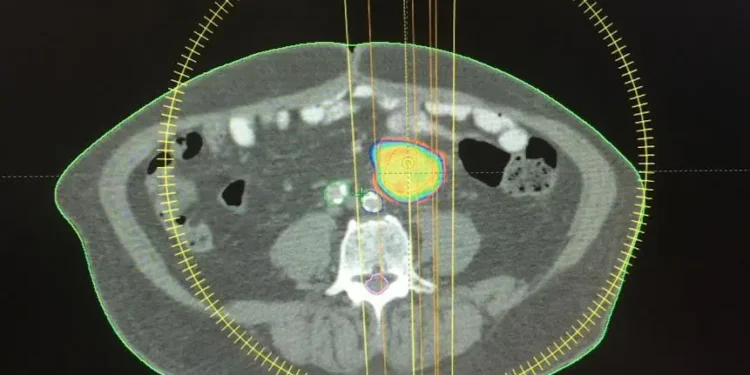

En 2015, especialistas del HOMS practicaron de manera exitosa la primera técnica de radiocirugía extracraneal, con avanzada tecnología en su Centro del Cáncer. La práctica se realizó en un paciente con metástasis ganglionar de primario colorrectal, utilizando PET-CT y tomografía de abdomen y pelvis con doble contraste, fusión de ambas imágenes y posterior verificación antes del tratamiento, mediante imágenes tomográficas del blanco a tratar.